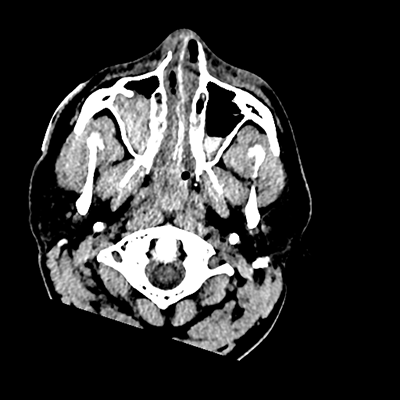

On day 5 of admission, he begins having intracranial hypertension again, spiking up to 40mmHg. You bolus with propofol and fentanyl, to no avail. You then push 30mL of 23.4% NaCl, which provides some brief improvement, allowing you to quickly get a non-contrast head CT. Unfortunately, he's now back up to 36mmHg. You review his labs, and note the following: Na 150, K 3.8, Cl 119, HCO3 18, BUN 21, Cr 0.85, glucose 136, sOsm 320.

NCHCT

NCHCT 3/20 3/20

NCHCT 4/20 4/20